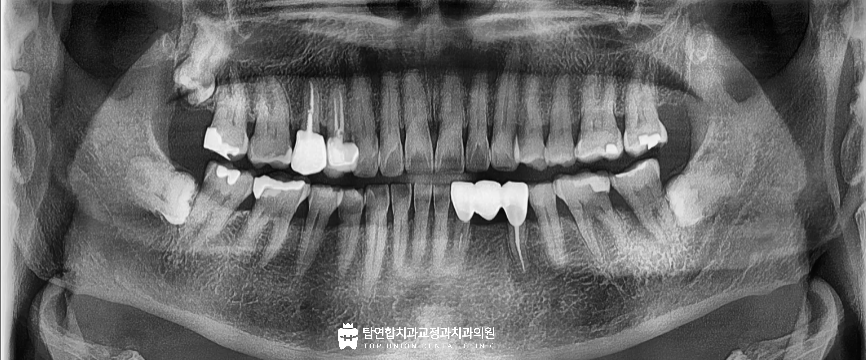

이번에 저희 병원에 내원해 주신 환자분은 60대 여성분으로

왼쪽 아래 어금니가 흔들리고 아프다고 하시면서

지인 소개를 통해 내원하였습니다.

첫 검진에서 치아가 아래위로 맞물릴 때

특정 지점에 힘이 몰리는 양상이 확인되었고

교합으로 인한 외상이 의심되었습니다.

간단한 씹기 검사에서 순간적인 찌릿한 통증 반응이 나타나

크랙 가능성도 함께 고려하였습니다.

작은 x-ray 사진에서는 해당 어금니의 근심 쪽 잇몸뼈가

까맣게 흡수되고 있는 모습이 보였고

잇몸 상태와 동요도 검사 결과를 종합해 분석한 결과

타원에서는 발치 후 임플란트를 설명 들었던 것과 다르게

치아를 살릴 수 있는 방향으로 치료 계획을 세웠습니다.

통증은 빠르게 감소했으며 x-ray 상에서 보였던

근심 부분의 파괴되었던 치조골이 회복 양상을 보였습니다.